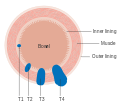

The T stages of bowel cancer.

The T stages of bowel cancer. Dukes stage A bowel cancer; the cancer is only in the inner lining of the bowel.